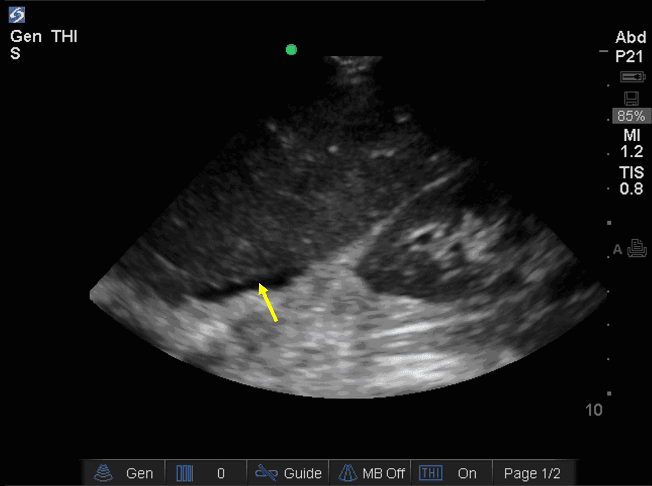

Upon arrival at the Level 1 Trauma Center, the patient remained tachycardic and demonstrated localized right lower quadrant peritonitis. A repeat E-FAST exam was positive for intraperitoneal free fluid in Morison’s pouch (see Figure 1). After further resuscitation, the patient was hemodynamically stable enough to undergo CT imaging of the abdomen/pelvis. The CT demonstrated a large right-sided retroperitoneal complex fluid collection measuring 82 x 132 x 172 mm that extended from the posterior pararenal space to the peritoneal fat anteriorly. Mottled locules of gas were evident within the collection, suspicious for traumatic colonic perforation. There was also fluid in Morison’s pouch (see Figure 2), consistent with what was seen on the E-FAST exam. As such, the patient was emergently taken to the Operating Room (OR) for exploratory laparotomy.